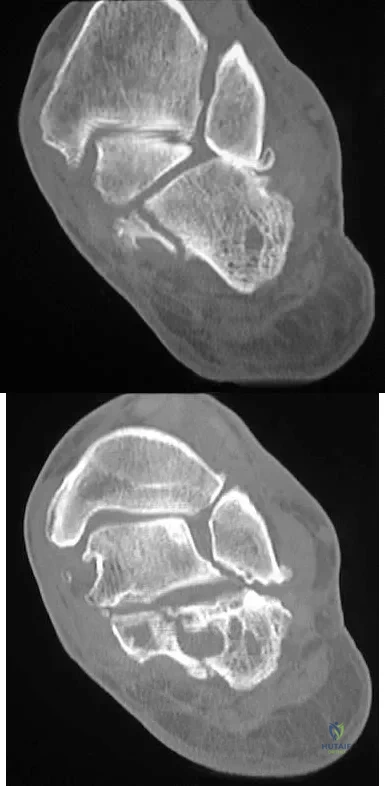

Question 98

A 50-year-old laborer sustained an isolated closed injury to his heel after falling 11 feet off a wall. A radiograph and a CT scan are shown in Figures 4a and 4b. To minimize the patient's temporary disability and allow him to return to work most rapidly, management should consist of

Explanation